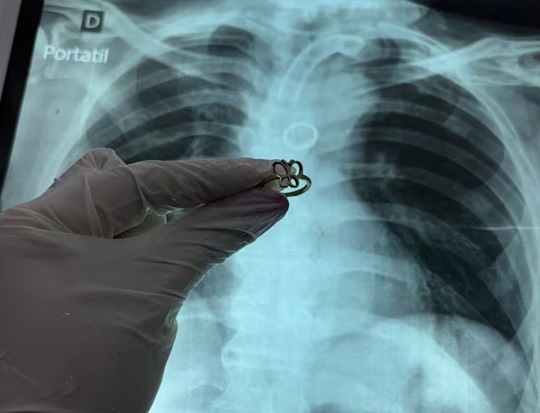

Un caso poco habitual sorprendió al equipo médico del Instituto Nacional de Enfermedades Respiratorias y del Ambiente (Ineram). Durante un estudio de rutina, profesionales detectaron un objeto extraño en el pulmón de un paciente de 54 años. Posteriormente, confirmaron que se trataba de un anillo de oro alojado en el bronquio.

En ese estudio se observó una imagen circular en el bronquio fuente izquierdo. En un primer momento, el hallazgo fue interpretado como un posible error técnico o un “artefacto” en la imagen. Sin embargo, una tomografía posterior confirmó la presencia de un objeto real en la vía respiratoria.

El neumólogo Carlos Morínigo relató que el equipo se encontró con “lo impensado”. Según explicó, se trataba de un anillo de oro de tamaño considerable alojado en el pulmón del paciente. Este tipo de hallazgo no es frecuente en la práctica clínica.

El médico describió el momento con una frase llamativa: “El anillo estaba brillando donde nunca debería estar”. El procedimiento se completó sin complicaciones, según el relato brindado por el equipo médico.

El anillo extraído del paciente.